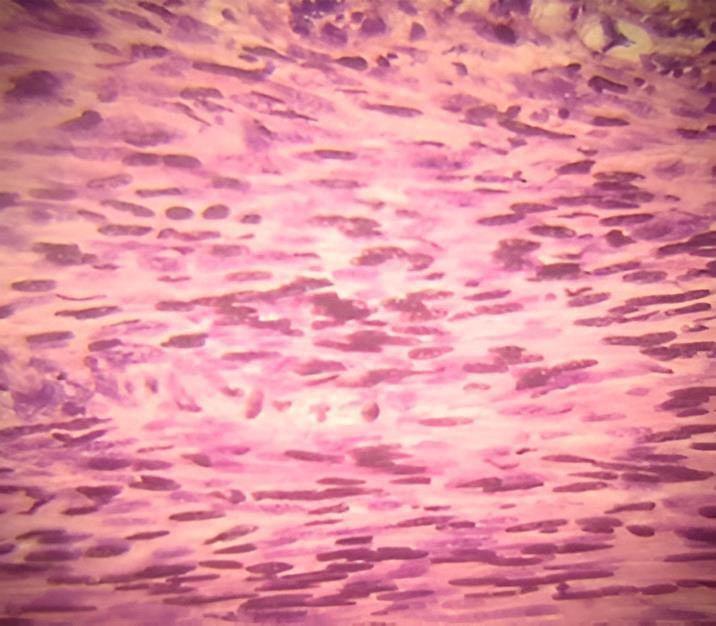

CortehistológicoconHyEa40X

Nota.Lesiónfusocelular,demoderadadensidad,concélulaspredominantementeelongadas,con núcleosovalesdecromatinagrumosaydepósitosdemelanina.

El estudio microscópico puso de manifiesto la existencia de una tumoración

constituida por células ahusadas pigmentadas bipolares con finas fibrillas dispuestas en haces entrecruzados, los núcleos celulares se disponen en filas transversales agrupadas por lo común en dos o tres corridas, entre las que el material fibrilar aparece hialinizado, estos grupos de núcleos dispuestos en empalizada junto a bandas hialinas son pleomórficos, con atípia leve. Las células tumorales presentan depósito citoplasmático disperso de melanina. (Figura 2).

El estudio microscópico puso de manifiesto la existencia de una tumoración constituidaporcélulasfusadasbipolarescon finas fibrillas dispuestas en haces entrecruzados, los núcleos celulares se disponen en filas transversales agrupadas porlocomúnendosotrescorridas,entrelas que el material fibrilar aparece hialinizado, estos grupos de núcleos dispuestos en

empalizada junto a bandas hialinas son pleomórficos, con atípia leve, algunas célulasmuestranensucitoplasmapigmento cafégrisáceo,entredichoshacessemuestra dicho pigmento en cantidad escasa. (Figura 4).